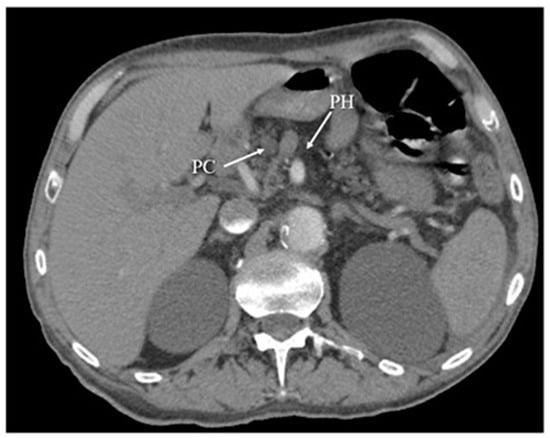

3.5. Computed Tomography

- Raghuwanshi, S.; Gupta, R.; Vyas, M.M.; Sharma, R. CT evaluation of acute pancreatitis and its prognostic correlation with CT severity index. J. Clin. Diagn. Res. 2016, 10, TC06. [Google Scholar] [CrossRef]

- Balthazar, E.J. Acute pancreatitis: Assessment of severity with clinical and CT evaluation. Radiology 2002, 223, 603–613. [Google Scholar] [CrossRef]

- Balthazar, E.J.; Robinson, D.L.; Megibow, A.J.; Ranson, J.H.C. Acute pancreatitis: Value of CT in establishing prognosis. Radiology 1990, 174, 331–336. [Google Scholar] [CrossRef]

- Mortelé, K.J.; Mergo, P.J.; Taylor, H.M.; Wiesner, W.; Cantisani, V.; Ernst, M.D.; Kalantari, B.N.; Ros, P.R. Peripancreatic vascular abnormalities complicating acute pancreatitis: Contrast-enhanced helical CT findings. Eur. J. Radiol. 2004, 52, 67–72. [Google Scholar] [CrossRef]